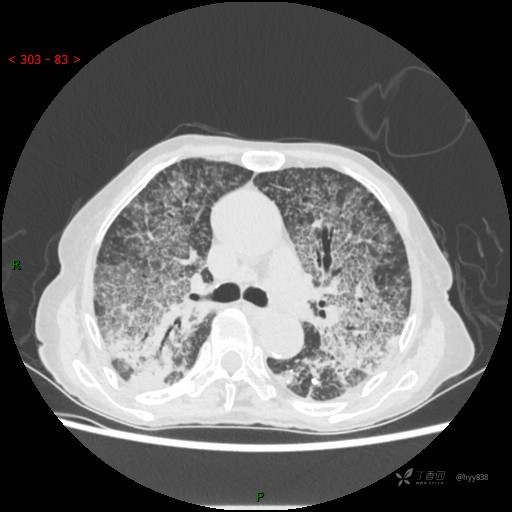

肺部弥漫性、疑难病变,感染或肿瘤?一元论或二元论?贴贴精彩---结果公布~

临床诊断:重症肺炎

胸部CT平扫